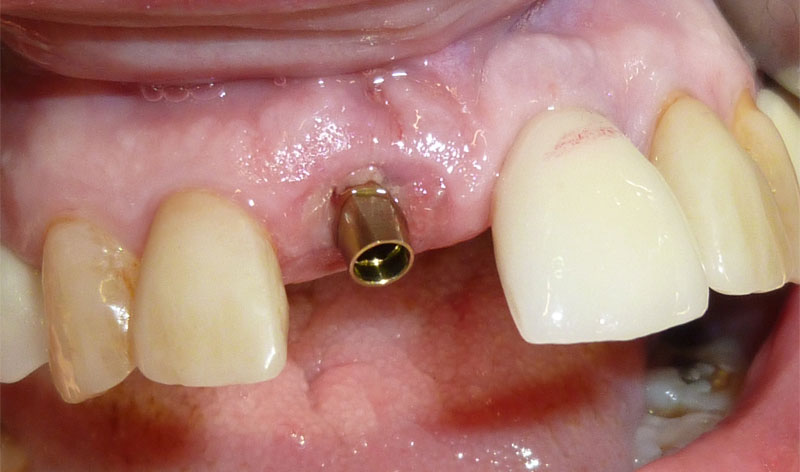

En estos casos han sido tratados con la filosofía de all-at-once, en la

misma sesión: